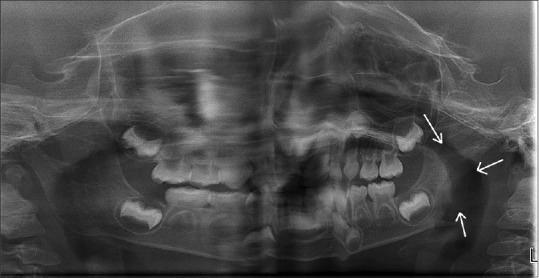

朗格汉斯细胞组织细胞增多症(LCH),也称为组织细胞增多症X或嗜酸性肉芽肿,是朗格汉斯细胞的一种局部或全身性异常克隆增殖性疾病。它具有广泛的临床表现,可发生在任何年龄组,以儿童和年轻人为主。这篇文章提出了一个罕见的病例LCH在一个2岁的女孩被暂时诊断为感染的颌骨不明病因。将临床、放射学和组织学特征与免疫组织化学分析相结合有助于得出LCH的明确诊断。口腔表现是大约5%-75% LCH病例中最早的表现,这强调了牙医在早期发现这种病变中的作用。由于朗格汉斯细胞病理浸润到各种系统,无数的临床光谱需要口腔诊断,然后进行全身扫描以检测任何系统累及。先进的靶向治疗可提高LCH患者的生存率和生活质量。

Langerhans cell histiocytosis (LCH), also called histiocytosis X or eosinophilic granuloma, is a local or systemic unusual clonal proliferative disorder of Langerhans cells. It has a wide spectrum of clinical presentations and can occur in any age group with predominance in children and young adults. This article presents a rare case of LCH in a 2-year-old girl child which was provisionally diagnosed as an infection of the jaw bone of unknown etiology. Correlating the clinical, radiologic, and histologic features with immunohistochemical analysis aided in arriving at a definitive diagnosis of LCH. Oral manifestations being the earliest presentation seen in around 5%-75% of LCH cases emphasize the role of a dentist in the early detection of this lesion. A myriad of clinical spectra due to pathologic infiltration of Langerhans cells into various systems necessitates oral diagnosis to be followed by a full body scan to detect any systemic involvement. Advanced targeted therapies can improve the survival rate and quality of life in patients with LCH.